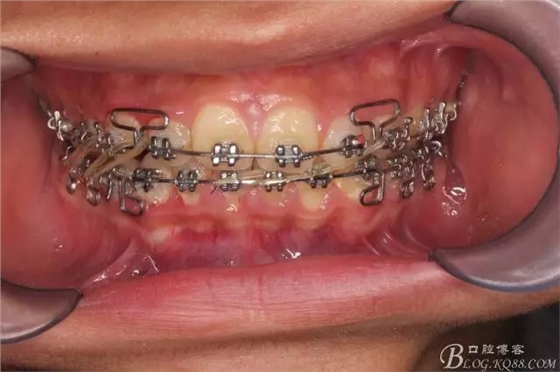

三度深覆合,三度深覆蓋,尖牙,磨牙均二類關(guān)系!

佩戴三個(gè)月的FR2, 效果奇佳!前牙基本達(dá)到淺覆蓋,淺覆合!接下來進(jìn)入二期直絲弓固定正畸,排齊階段!